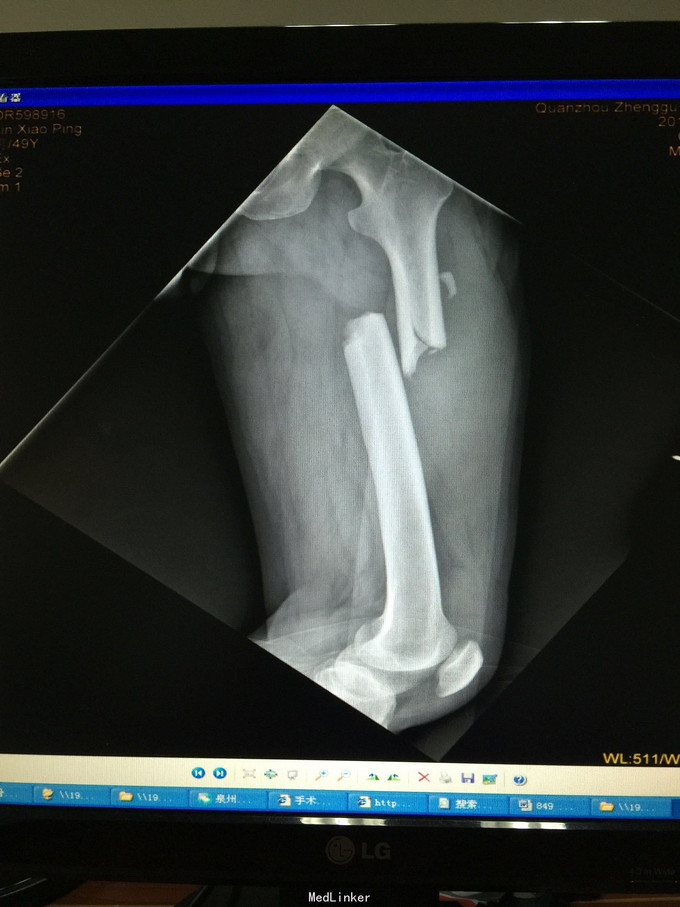

左股骨中上段骨折术后骨不连

主诉:左股骨骨折术后伴局部酸痛11个月

术后半年 讨论 考虑股骨中上段骨折 应力集中 近段一枚螺钉稳定性不够?